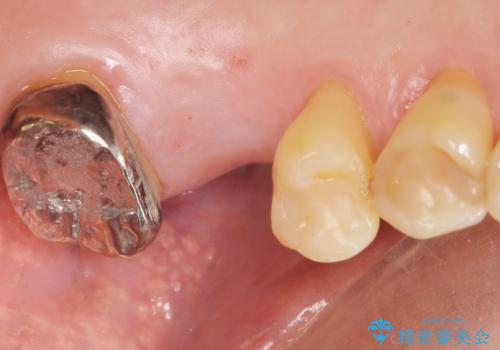

審美的・機能的な仕上がりに喜んで下さいました。

また、半年という比較的短期間でインプラント治療が終わったことにもご満足頂けました。

インプラントの種類:スプライン ツイスト (保証期間:5年)

クラウンの種類:ベレッツァクラウン (オールセラミック)

固定様式:セメント固定